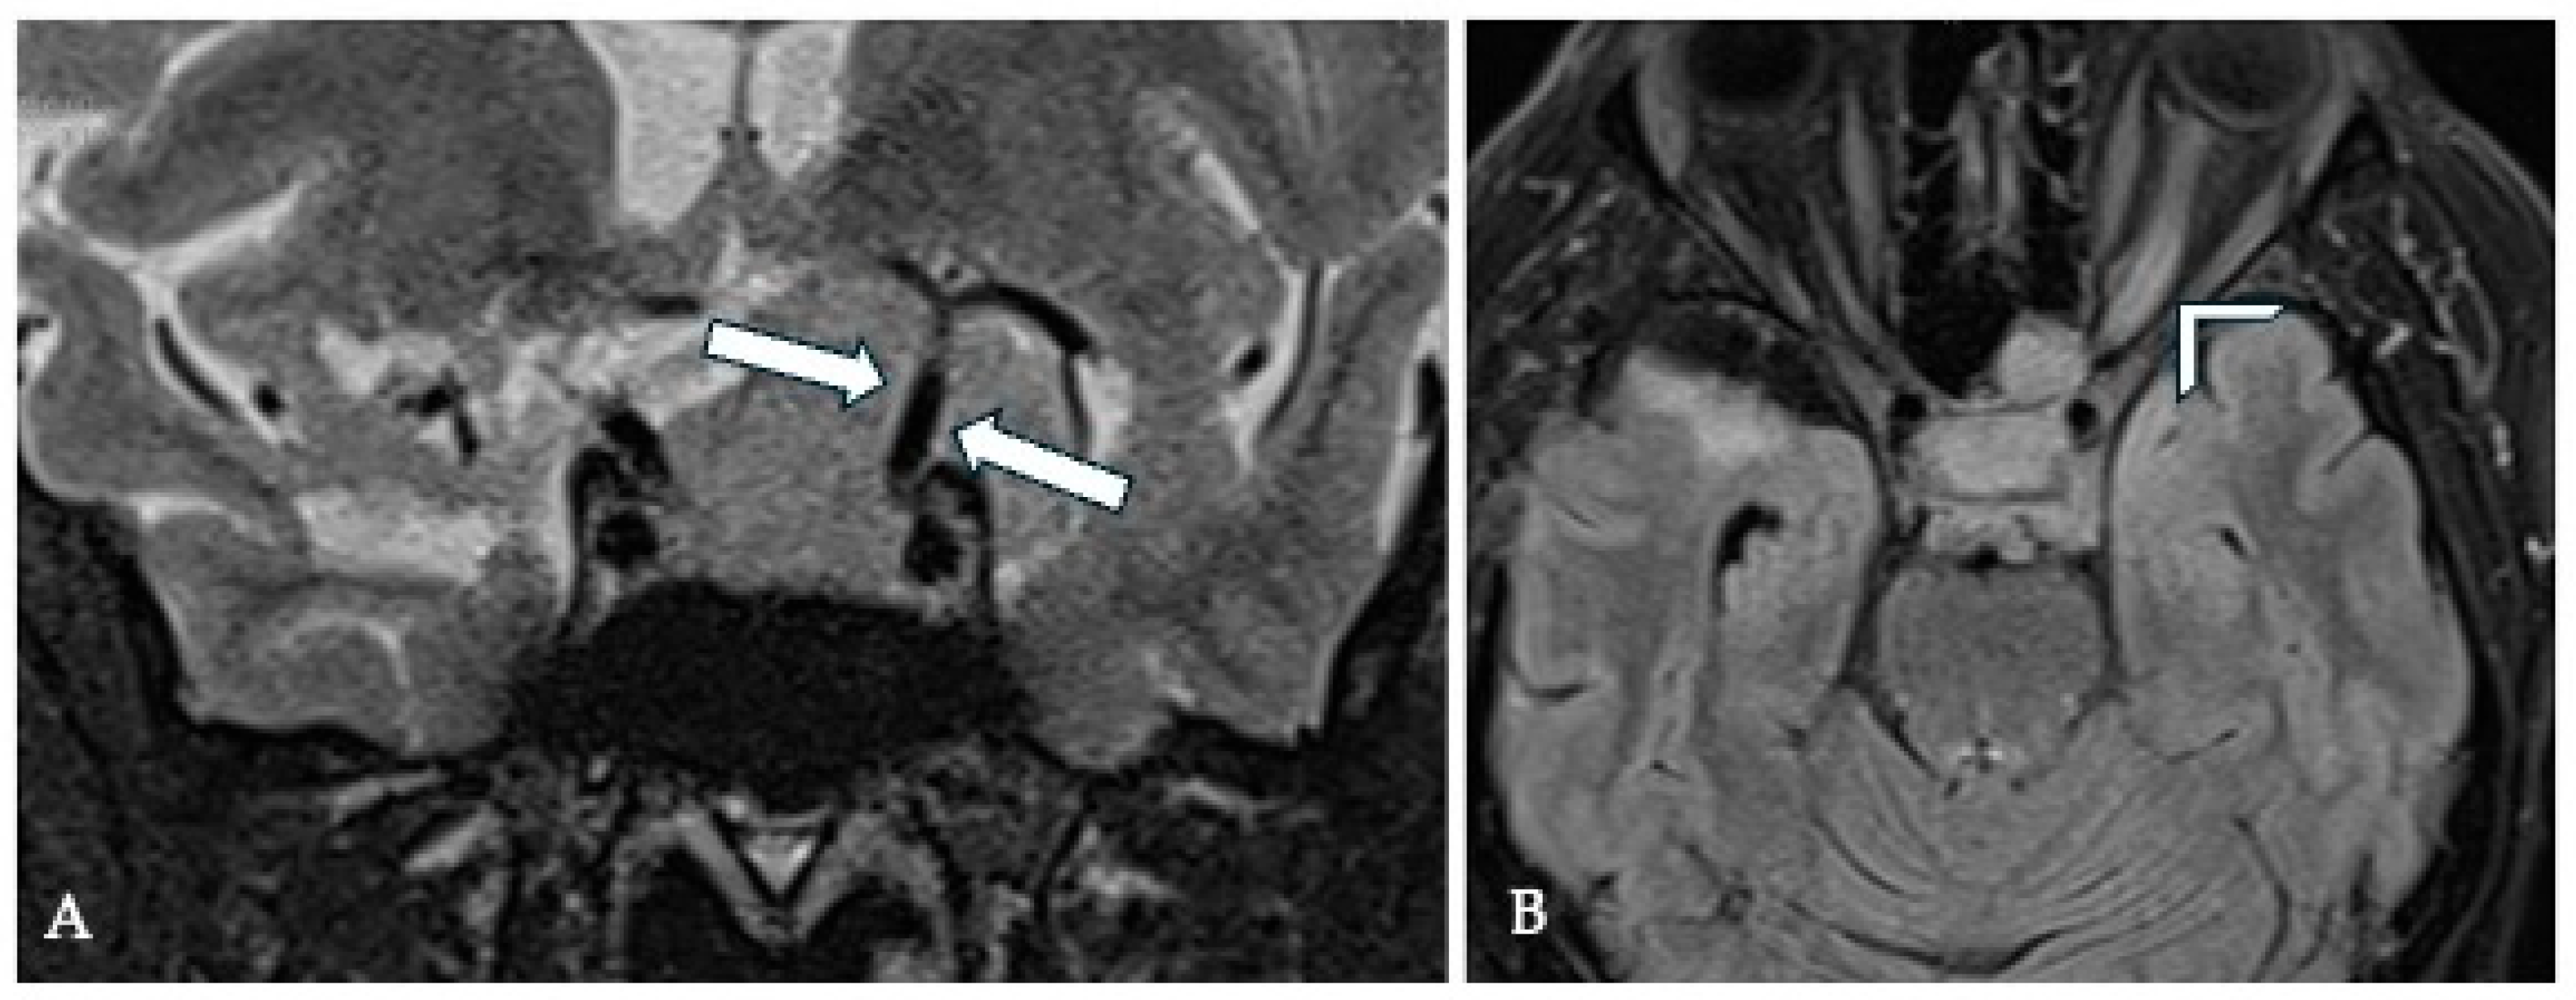

7.2. Imaging Evaluation

8.2. Imaging Evaluation